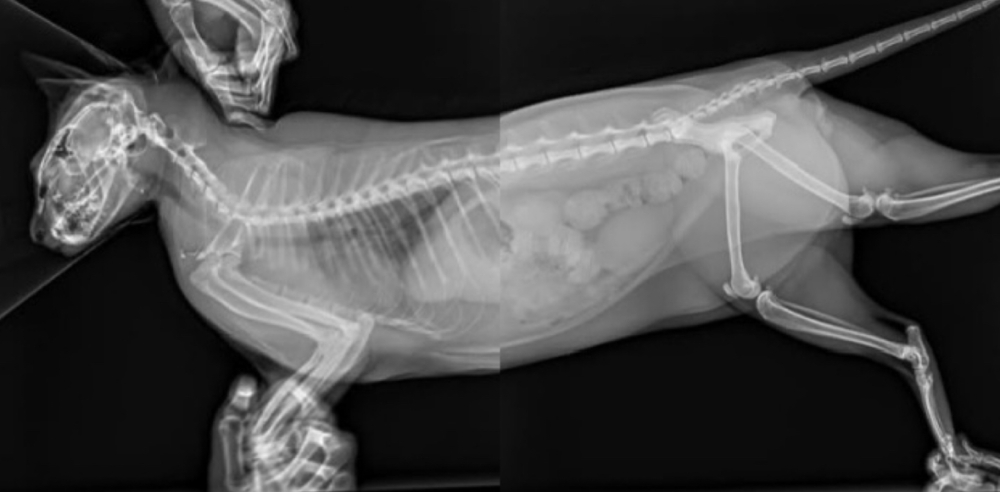

事後,貓咪的飼主帶牠到獸醫院檢查,結果顯示牠的健康狀況良好,僅有兩隻爪子出現輕微的傷口。即便如此,師傅的食欲依然旺盛,情緒穩定,完全沒有受到驚嚇,依舊表現得十分活潑,讓所有人都鬆了一口氣。